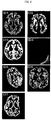

• FIG 4 shows examples of a normal tissue segmentation result and segmentation errors.

• ID1 to ID7 are axial (horizontal section) slice images, and the gray matter parts are shown in white, while other parts are shown in black.

• ID1 is the normal example

• ID2 to ID7 are the segmentation error examples.

• the causes of segmentation error vary, such as movement of the test subject during imaging, deviation in imaging position, and wrong imaging condition.

• the image of ID2 contains too much white matter. This can be understood when observed by comparing with the image of ID1.

• parts which should be extracted as white matter are extracted as gray matter in the tissue segmentation process.

• the image of ID3 contains too much cerebrospinal fluid. This can be understood when observed by comparing with the image of ID1.

• parts which should be extracted as cerebrospinal fluid are extracted as gray matter in the tissue segmentation process.

• the image of ID4 shows almost no gray matter. This can be understood when observed by comparing with the image of ID1.

• parts which should be extracted as gray matter are extracted as white matter or cerebrospinal fluid in the tissue segmentation process.

• the image of ID7 is lacking a large area. This can be understood when observed by comparing with the image of ID1. In the image of ID7, it appears that the imaging area was not correct or that there was a defect in part of the imaging data.